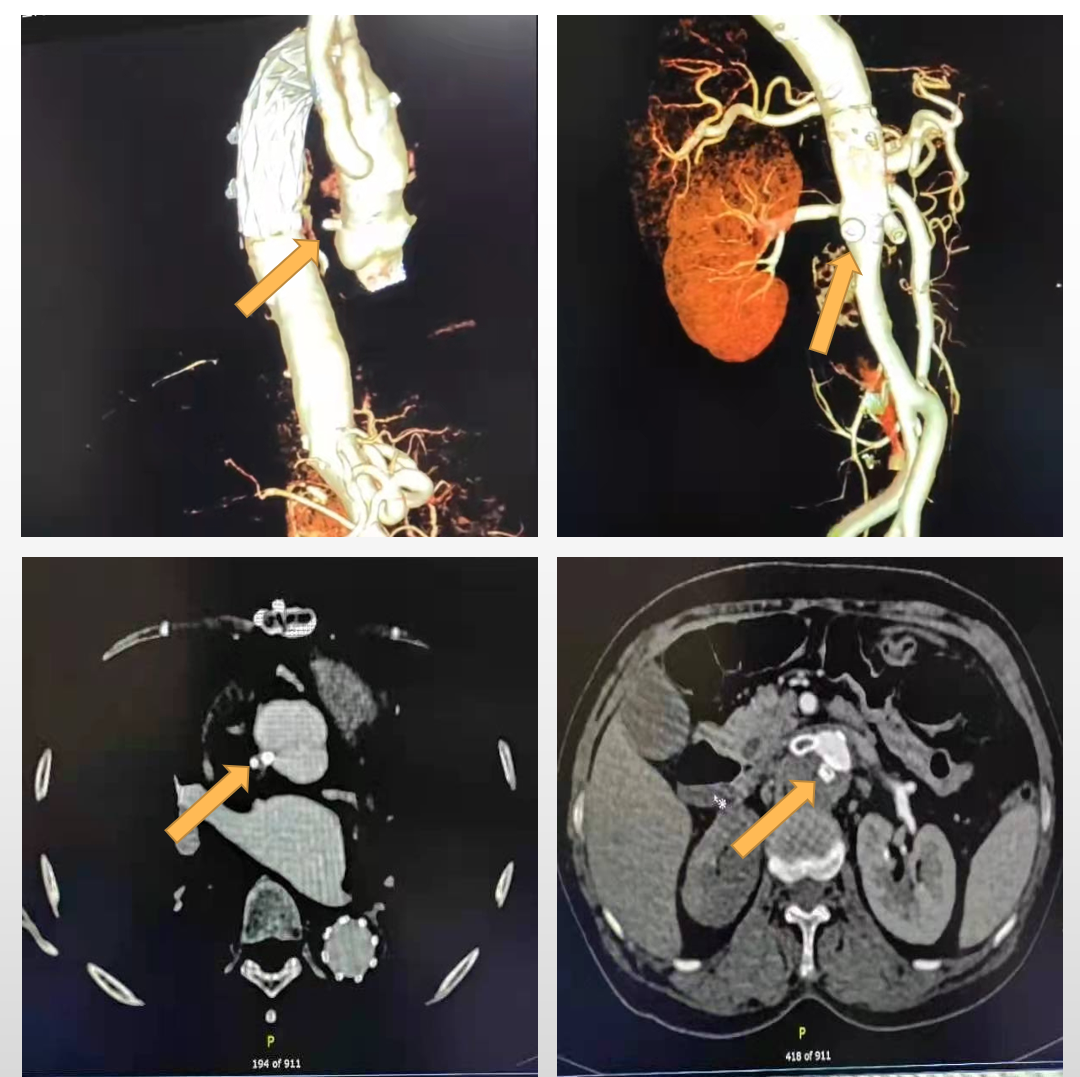

图4.术后随访CTA影像(箭头所指为升主动脉及腹主动脉血管塞)

该病变采用传统的治疗方式,可能需要再次开胸修复升主动脉破口,腹主夹层需要复杂的保留内脏动脉的支架开窗或主动脉置换手术,手术困难复杂,风险高,并发症多,且花费高昂。新的技术方案解决了很多难题:微创,只经股动脉穿刺入路,在血管腔内用血管塞封堵夹层破口;并发症少,避免覆膜支架或手术阻断大量肋间动脉及腰动脉,减少截瘫发生率;花费低,较传统手术或腔内治疗降低2-3倍。该治疗方案适用于破口较小的A型及B型的主动脉夹层,对于破口大的夹层不适合(缺少大规格且异形的血管塞),慢性期更加安全,或可作为复杂夹层的辅助治疗方案。

A型主动脉夹层行血管塞腔内修复手术,在选择性病人中是可行且安全的,其治疗思路及技术操作具有一定的创新性,值得在专业领域进一步应用和推广。